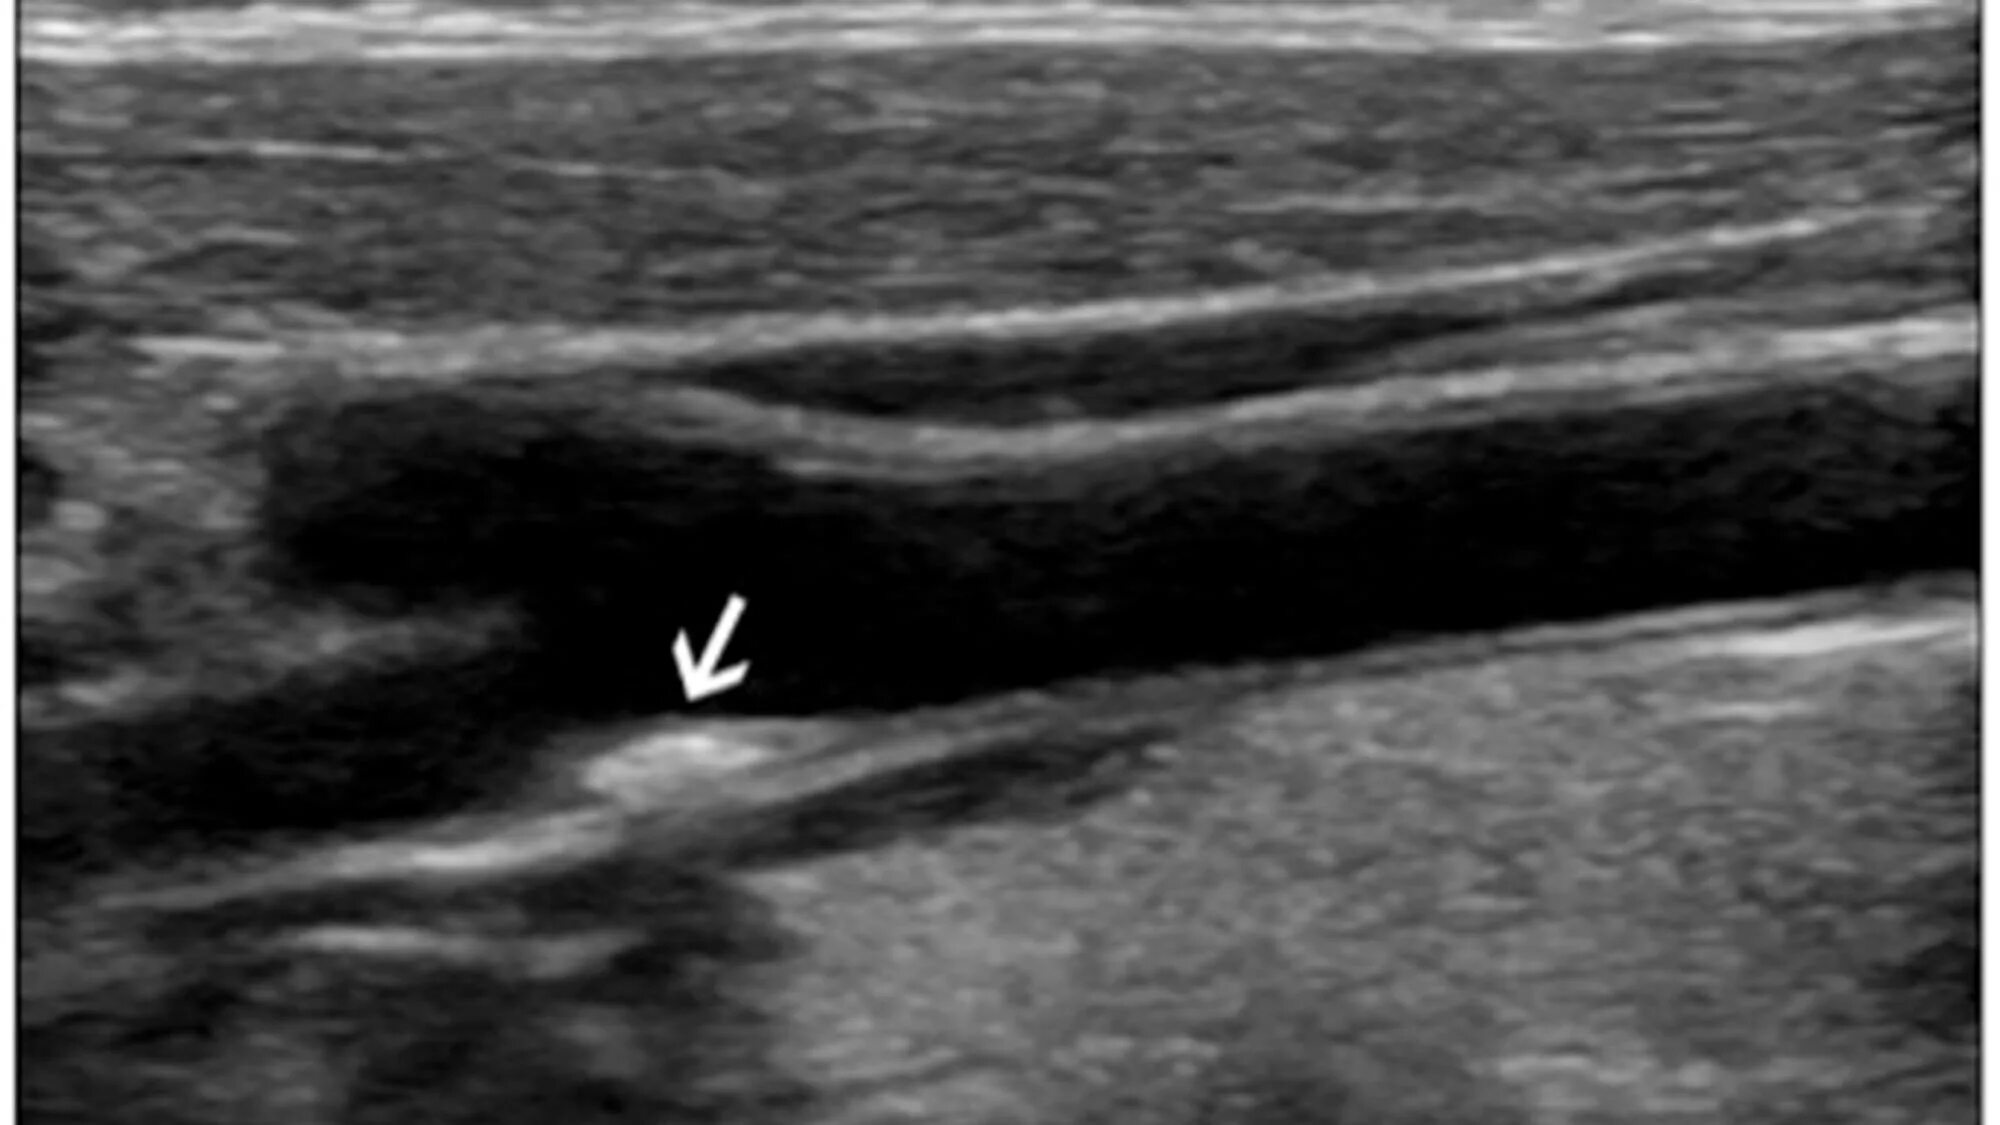

Атеросклероз на узи